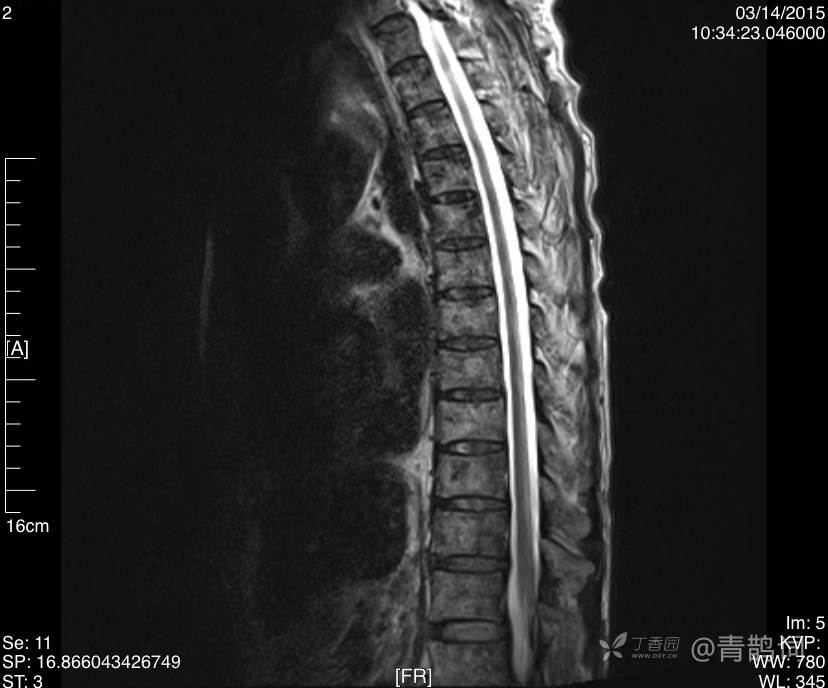

影像学检查如下:

T2矢状位: